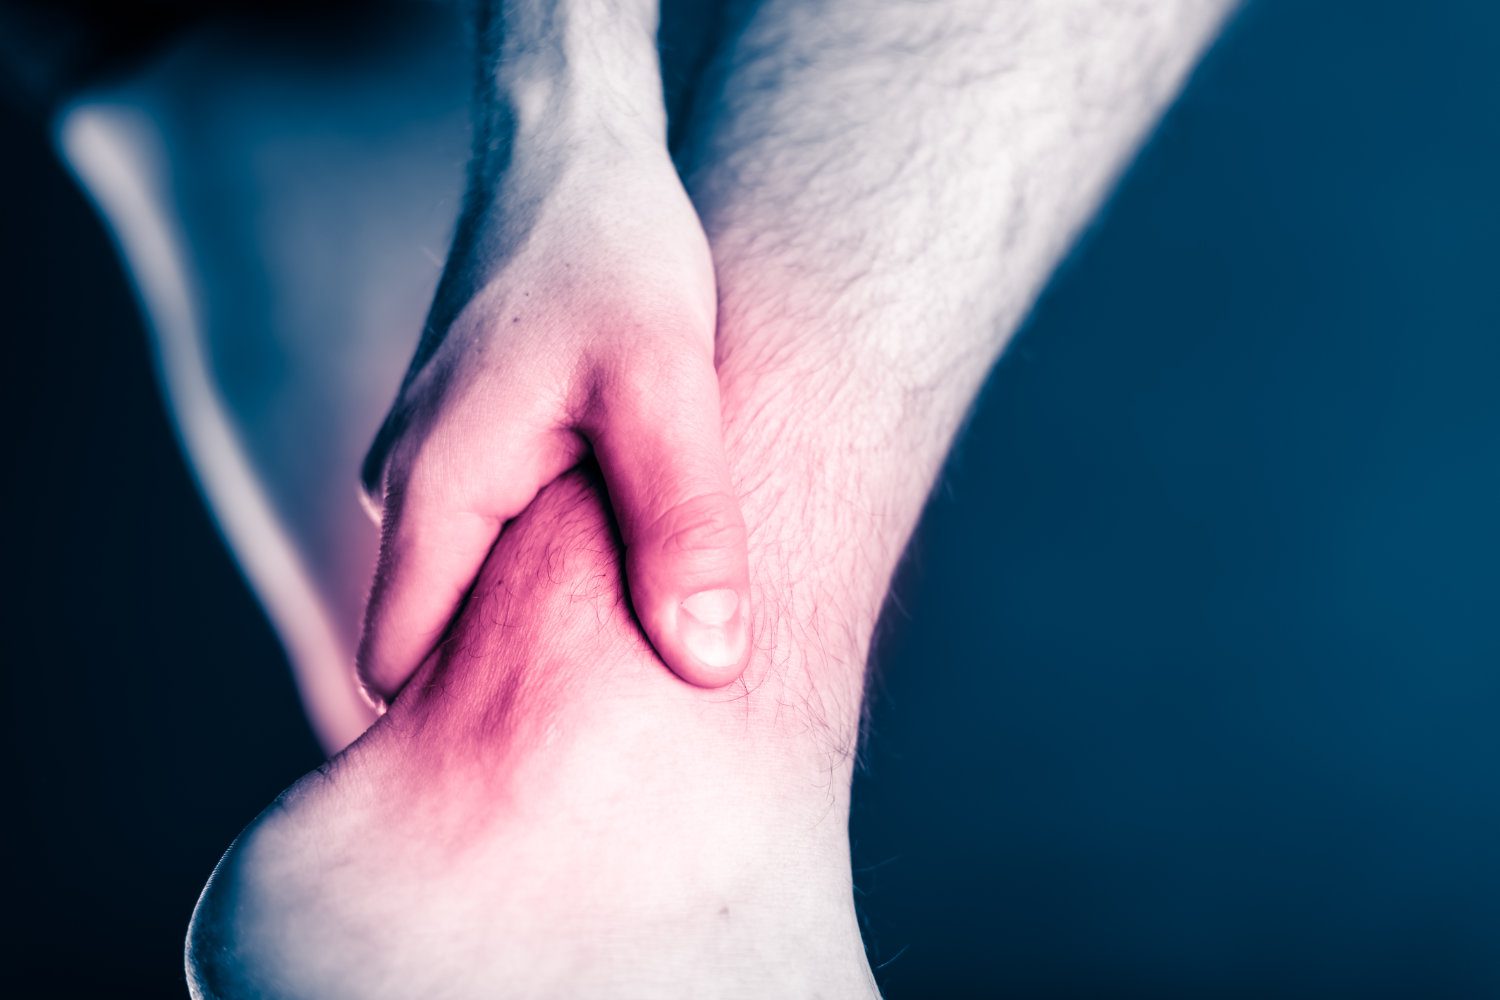

Ankle Pain

Pain at the ankle is usually caused by local structures within or around the ankle, however in rare ...